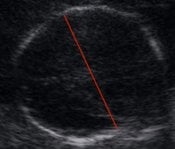

Fetal kafa ölçümünün normal değerleri

Hafta

alt sınır

(%5)

mm

Ortalama

(%50)

Üst sınır

(%95)